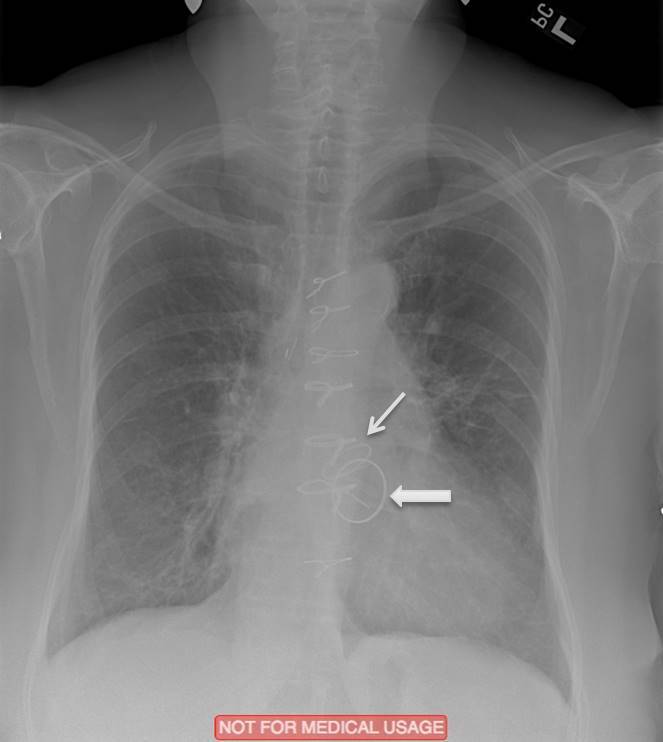

What are the indicated valves?

What valves are indicated?